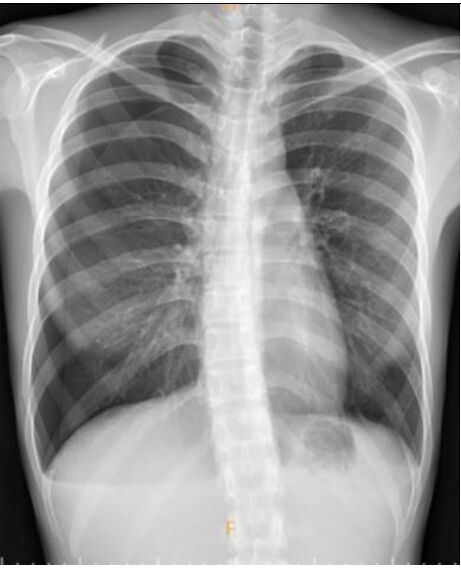

4. 病人是位29歲男性電子工程師派駐中國深圳,三個星期來,時有間歇性發燒及逐漸性呼吸困難,先在深圳 門診求醫,初以為一般感冒治療,後以支氣管炎診斷治療罔效,乃急回台灣求醫。經檢查,意識: E4M6V5; BP: 122/75 mmHg; PR: 116/min; RR: 21/min; Temperature: 37.6℃; SPO2: 94%(room air) 頸靜脈不怒張,未有貧血,胸部呈現瀰漫性濁音,心臟擴大,有Grade III/VI Diastolic murmurs at left upper sternal border,無肝脾腫大,無腹水。皮膚未有紅腫或出血斑點。2016/12/23心電圖及胸部X光如 圖。其血液、尿液及生化如次:Hemograms: WBC, 13.54(k/uL); RBC, 4.74(M/uL); Hb, 13.0 (gm%); HCT,40.2(%); MCV, 84.8 (fL); MCH,27.4(pg); Platelet,329 (k/uL); Seg, 81.5(%); Eos, 0.2(%)。尿檢: 正常。請 問這位年青病人的最可能診斷是:

(A) Acute heart failure with lungs infection。 (B) Acute pericarditis。 (C) Acute viral myocarditis。 (D) Acute infective endocarditis。 (E) Acute pulmonary thromboembolism。